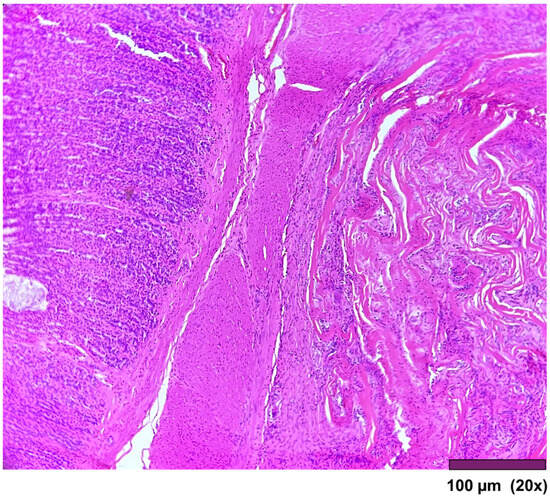

The stomach wall showed (Figure 5) minimal architectural difference between the native and the regenerated stomach fragment, with mild fibrosis and moderate infiltration of inflammatory cells in the subserosal layer. In one sample, the SIS-covered stomach portion of the muscularis propria was replaced by a thick layer of fibrosis (Figure 6).

Figure 6. Stomach: Muscularis propria was replaced by a thick layer of fibrosis (20×, HE).